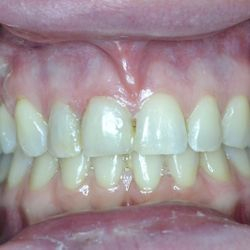

Το 9χρονο αυτό κοριτσάκι έσπασε τους κεντρικούς άνω τομείς μετά από πτώση στο έδαφος.

Τα δόντια απονευρώθηκαν και στη συνέχεια αποκαταστάθηκαν με συνδιασμό τοποθέτησης ενδοριζικών αξόνων και ανασυστάσεων σύνθετης ρητίνης.

Συγκεκριμένα, άξονες υαλονημάτων τελευταίας τεχνολογίας (ParaPost FiberWhite/Coltene και FiberCone/RTD) συγκολλήθηκαν εντός των ριζών και τα δόντια ανασυστήθηκαν με νανουβριδική σύνθετη ρητίνη (Herculite XVR Ultra/Kerr) με την βοήθεια ειδικής μήτρας/οδηγού από σιλικόνη.

Το χαμόγελο της μικρής ασθενούς μας αποκαταστάθηκε άμεσα όπως είναι εμφανές στην τελευταία φωτογραφία.